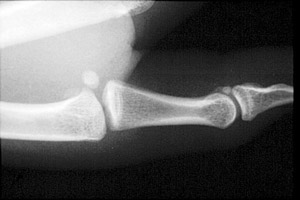

- Click on the image for a larger versionBLateral radiograph of the first digit. This patient demonstrates the findings of gamekeeper's thumb with mild subluxation at the MCP joint.